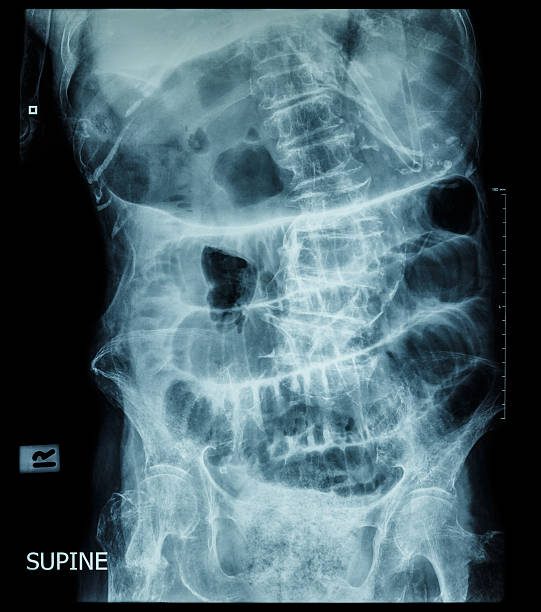

장폐색 치료법은 장폐색의 심각도와 증상의 정도, 환자의 건강상태 등에 따라 다양하게 시행됩니다. 주로 다음과 같은 방법이 사용됩니다.

- 약물치료: 혈압강하제, 항응고제 등을 투여하여 혈액순환을 개선하고 새로운 혈전 형성을 예방합니다.

- 혈관확장술: 도관술, 혈관 스텐트 삽입, 혈관성형술 등을 이용하여 혈관을 확장하거나 협착된 부분을 개선합니다.

- 수술: 치료가 어려운 경우나 합병증이 있는 경우 등에는 수술적 치료가 필요합니다. 부위에 따라 다양한 수술 방법이 있습니다.